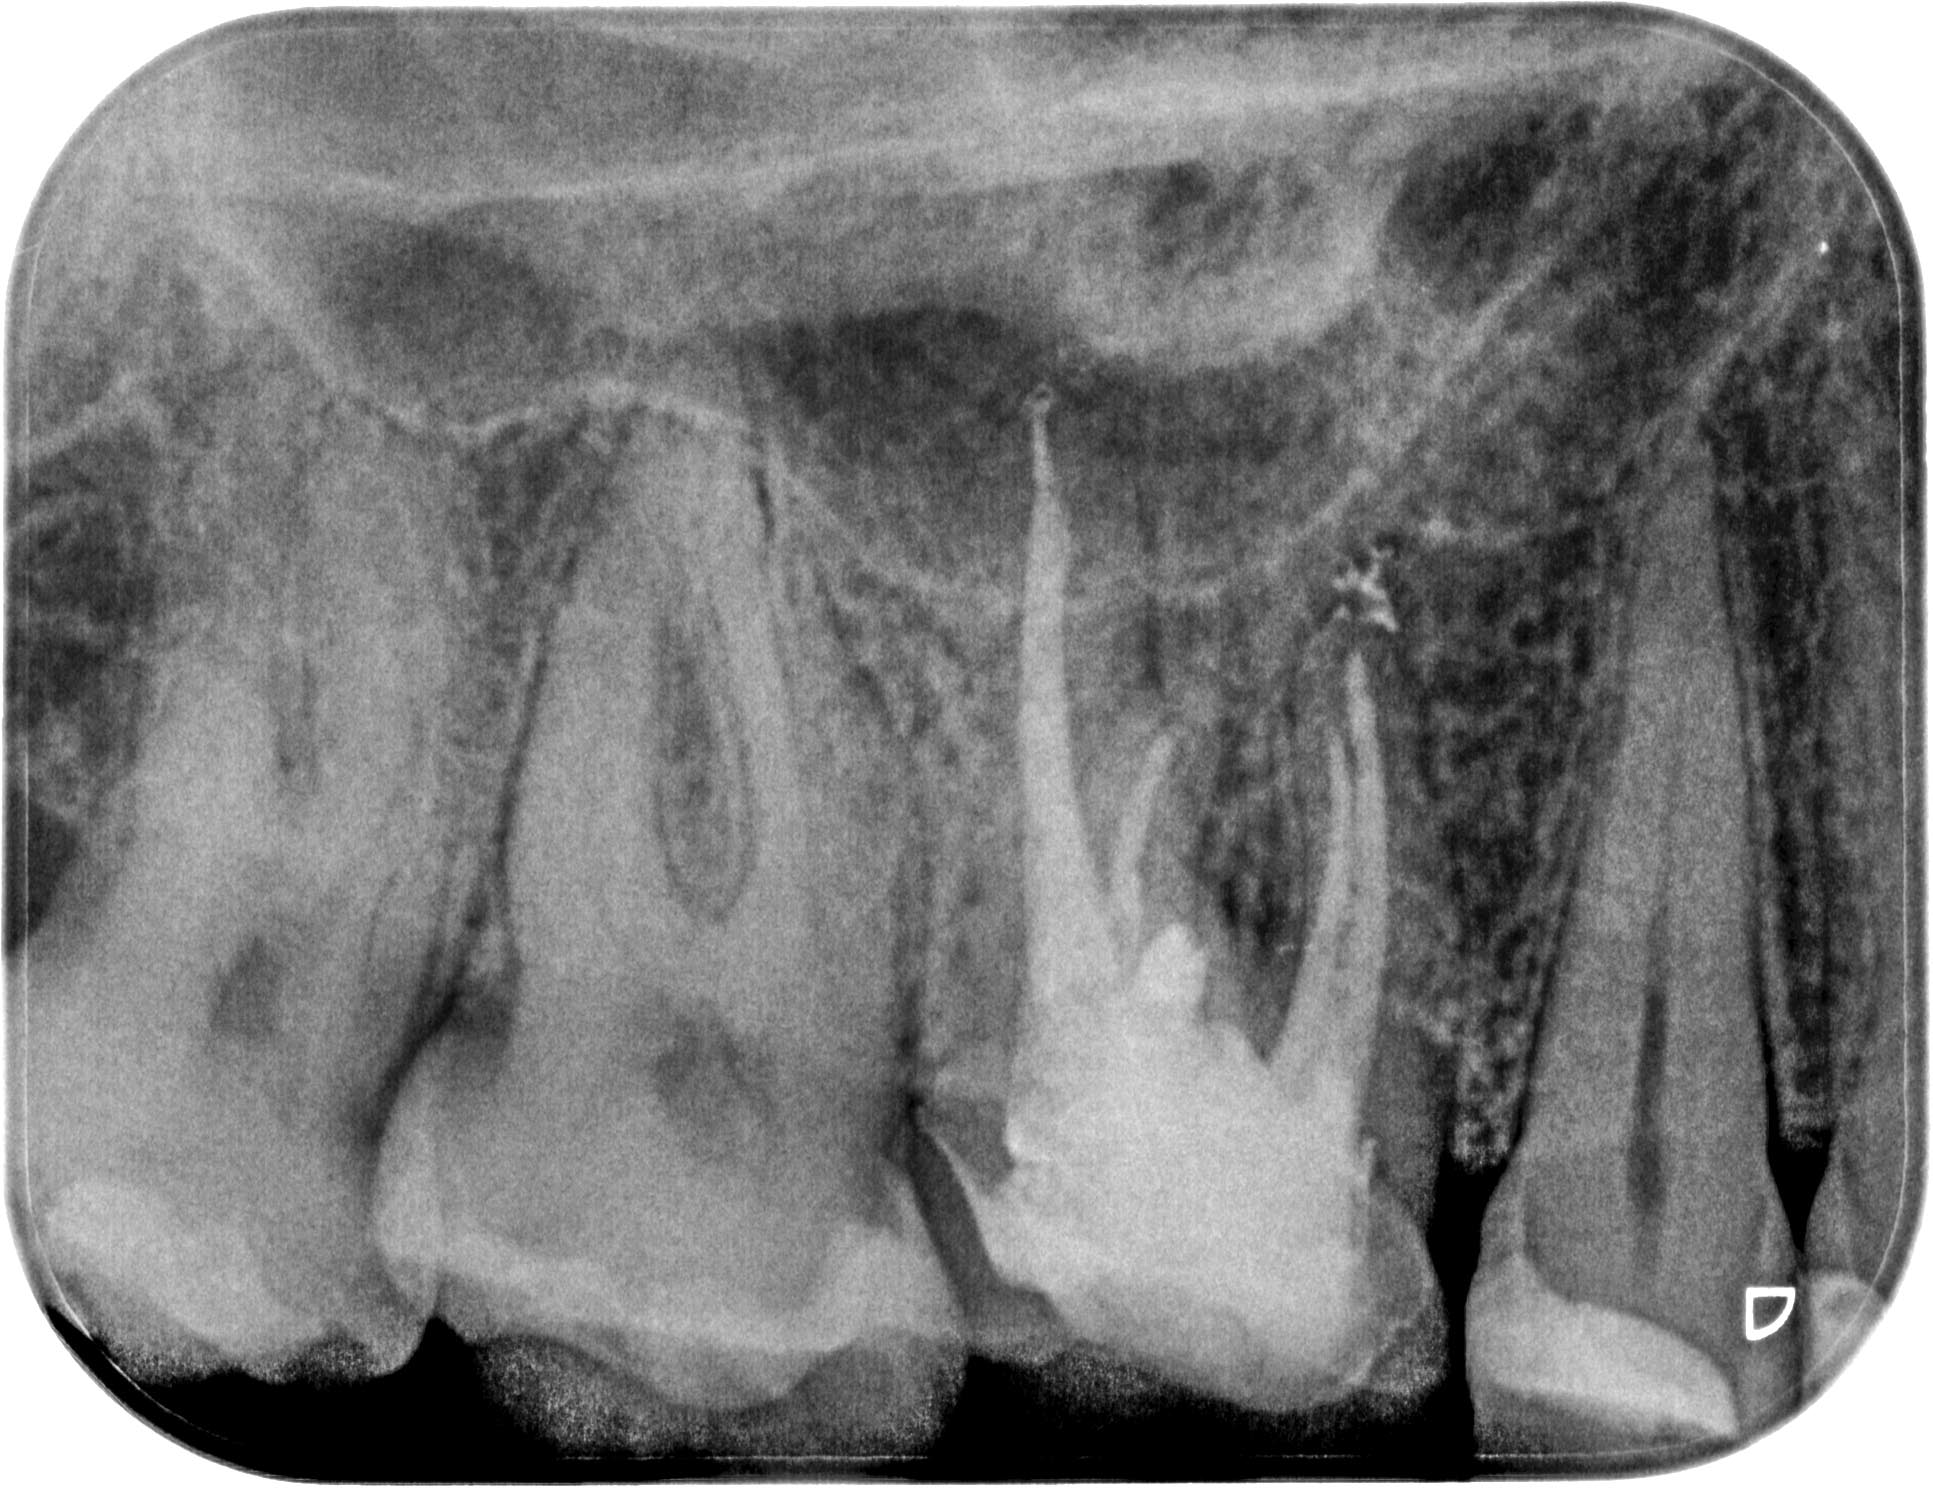

gs_wf_20151120-1 Veröffentlicht 25. Oktober 2016 am 1933 × 1492 in Unauffälliges Röntgenbild (Teil 2)